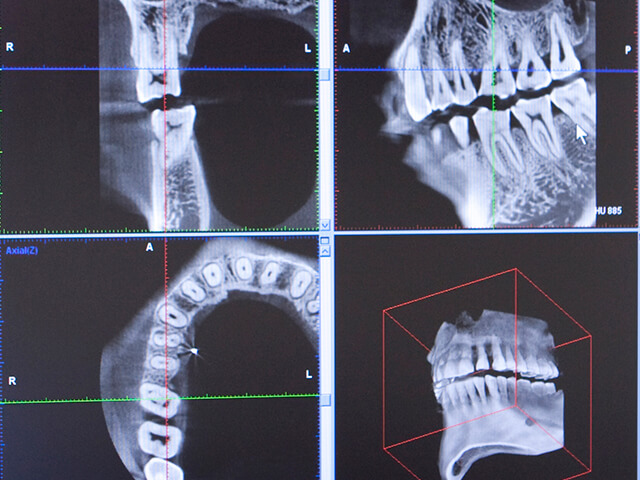

| 検査料 | 検査・診断料 | 82,500円~ |